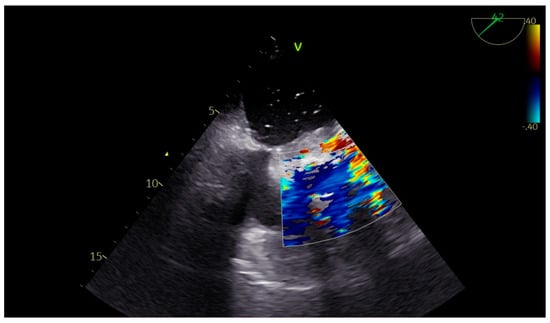

Advanced hemodynamic monitoring as per local protocol was applied with cannulation of the right radial and femoral arteries as well as establishment of peripheral access with two (wide) 16 G cannulae. Baseline invasive blood pressure before induction was 145/60 mmHg. Induction to anesthesia was uneventful without any signs of hemodynamic instability, using balanced anesthetics for the maintenance of general anesthesia too. A central line and pulmonary artery catheter were placed in the right internal jugular vein. Continuous cardiac monitoring and cerebral oximetry monitoring were applied while depth of anesthesia was monitored with the Bispectral Index. Intraoperative transesophageal echocardiography (TEE) was used and confirmed the findings of TTE, especially with a heavily calcified mitral valve annulus (Figure 1). Standard bicaval extracorporeal circulation through sternotomy and mild systemic hypothermia (32 °C) were used. Myocardial protection was made by a combination of antegrade and retrograde cold hyperkalemic blood cardioplegia. Cardiopulmonary bypass time was nearly two hours. The separation from cardiopulmonary bypass was initially smooth with minimal vasopressor support (blood pressure > 85–90/45 mmHg). A few minutes after the protamine administration an episode of profound hypotension caused major hemodynamic instability (blood pressure > 55–60/35 mmHg), which was related to the protamine side effects. However, since it persisted, regardless of the treatment with vasopressors, a thorough reassessment with the TEE was performed. This dynamic investigation revealed an obvious flap fluctuating in the left atrium, suggestive of a dissection flap in the chamber (Figure 2). (The dissection flap size was at least 7.2 cm. There was difficulty in the precise measurement of its dimension because the left atrium roof could not be visualized.) Otherwise, the two new prosthetic valves were well seated without any residual regurgitation (Figure 3 and Figure 4). The most plausible explanation for the presence of the dissection flap was the earnest mitral valve replacement performed in the setting of extensive mitral annular calcification. Hemodynamic stability was achieved with boluses of vasopressors (phenylephrine) and noradrenaline and adrenaline infusions. Since the patient was relatively stabilized under this support, the chest was closed and he was taken to the intensive care unit with a target for systolic blood pressure less than 100–120 mmHg for the first twenty-four hours (Table 1).

Figure 2. Left atrial dissection flap.

Figure 3. Color flow Doppler showing a competent prosthetic mitral valve in place with dissection flap in the left atrium.